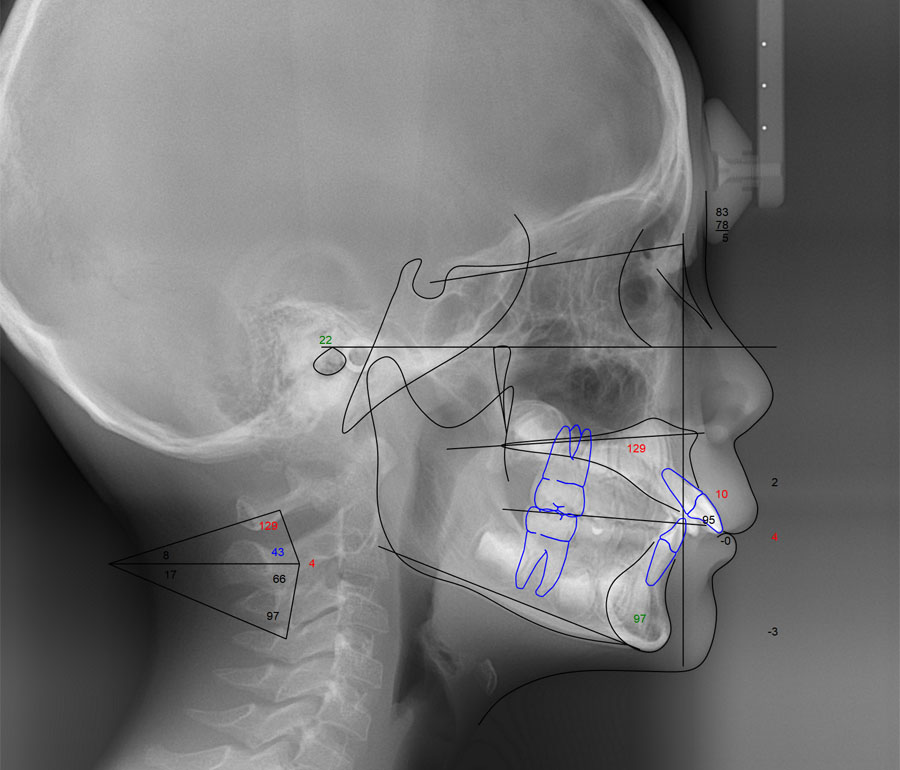

採得したデジタルデータを、コンピュータ解析します(セファロ分析および治療シミュレーション)。 また上下顎骨の前後的および垂直的バランスを評価し、今後の成長を考慮した上で治療方針を決定します。 サリバテストでは、口腔内の細菌と唾液の性質を評価し、現在の口腔内環境に合わせた虫歯予防プランを作成します。 検査結果を元に十分な相談の上、できる限り希望に沿えるよう適切な治療の計画を立てます。

セファロ分析

頭部X線規格写真